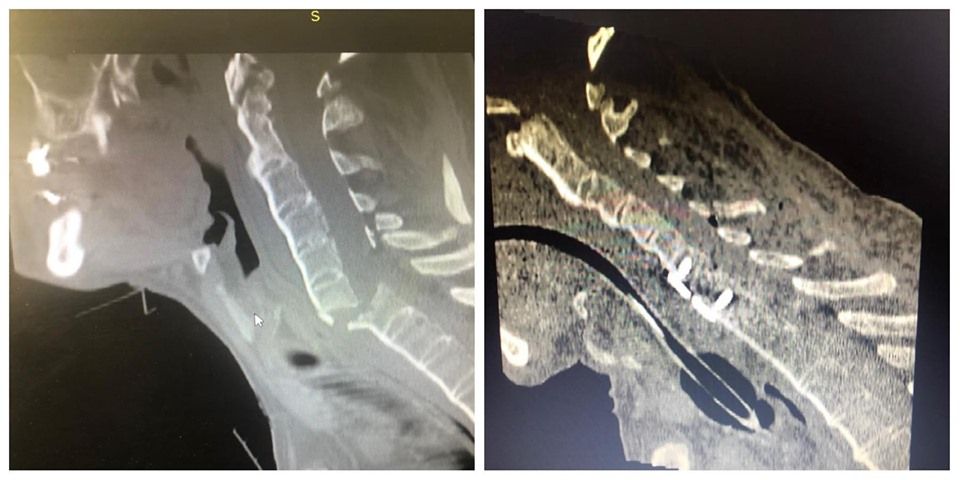

În imagini se poate vedea coloana vertebrală a pacientului, înainte și după operație.

Potrivit managerului Spitalului Județean de Urgență Bistrița, Gabriel Lazany, este vorba despre un pacient care a suferit o fractură cervicală complexă în urma unui accident de bicicletă.

Potrivit sursei citate, intervenția chirugicală a durat aproximativ 5 ore. ”Intervenția a necesitat prezența intraoperatorie a trei medici neurochirurgi: dr. Andrei Farcaș, dr. Estera Pop și dr. Florin Leaț și a doi medici anesteziști: dr. Julien Antohi și dr. Anatol Burlacu. Pacientul a fost transferat luni la Bistrița cu ambulanța fiind în stare foarte gravă, marți a avut loc cu succes intervenția chirurgicală, iar miercuri a fost transferat înapoi la spitalul de proveniență”, a mai adăugat Lazany.